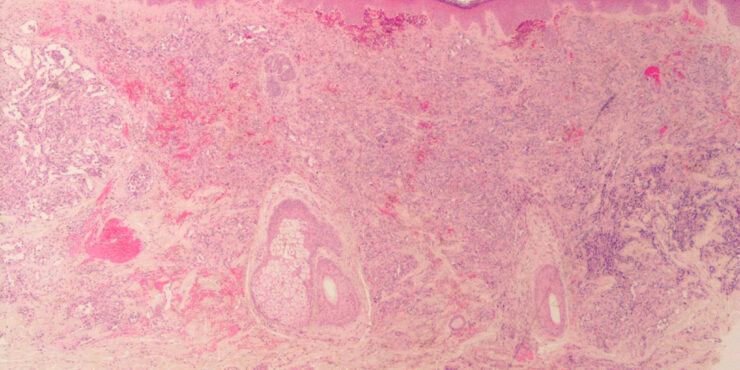

Read MoreApocrine hidrocystoma =الكيسوم العرقي المفترز Apocrine hidrocystoma The clinical appearance of a pea-sized cyst near the inner canthus of the eye, which contains a thin clear or pigmented fluid, suggests an apocrine hidrocystoma; however, histologic examination often is required to establish a specific and definitive diagnosis. Upon histologic examination, apocrine hidrocystomas show large unilocular or […]